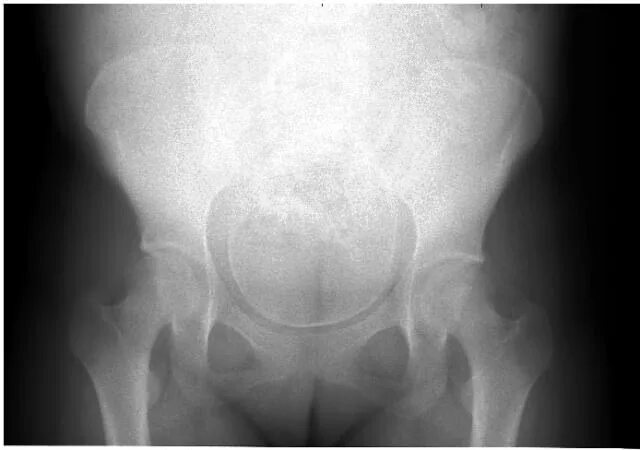

Делала рентген при беременности